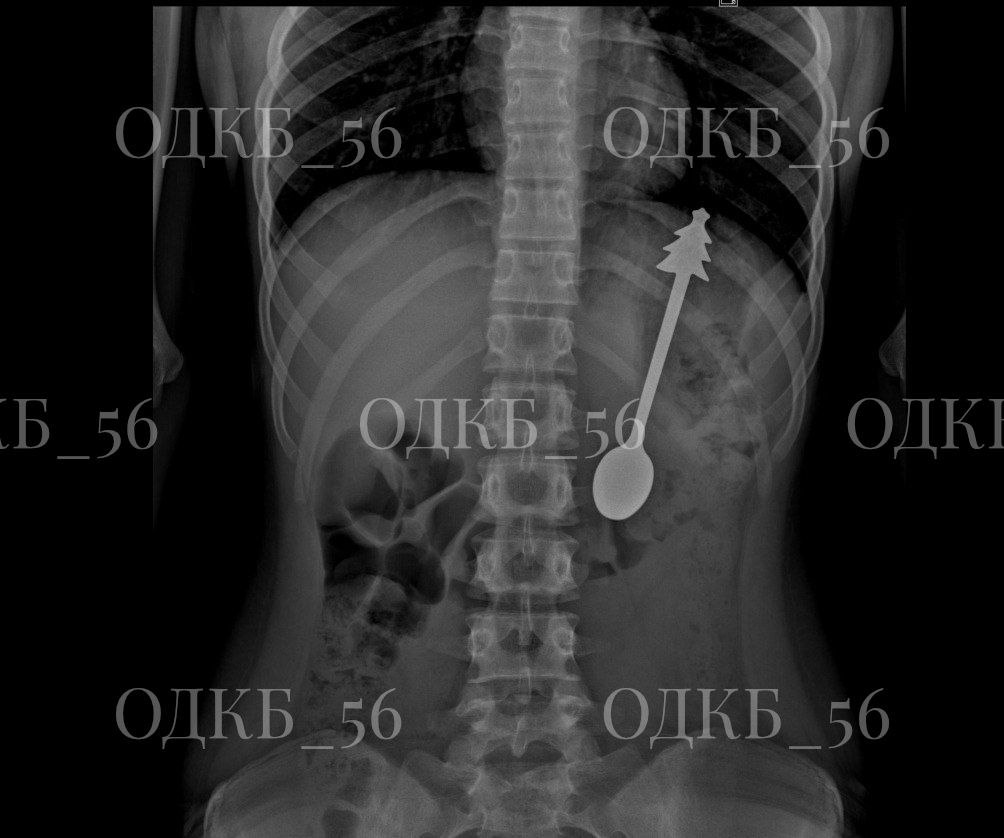

В Областную детскую клиническую больницу бригада скорой помощи доставила ребёнка, который случайно проглотил… металлическую ложку.

Диагноз был подтверждён мгновенно: рентген показал инородное тело в желудке. Малыш был экстренно госпитализирован в хирургическое отделение.

Под общим обезболиванием команда хирургов-эндоскопистов провела операцию: с помощью ЭГДС была аккуратно извлечена ложка длиной 14 см! Всё прошло успешно, без осложнений, и уже на следующий день ребёнок был выписан домой в отличном состоянии.

Фото: ОДКБ